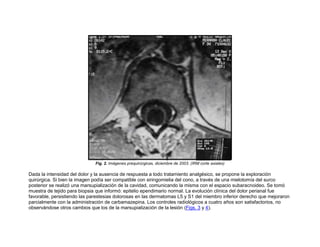

Fig. 2. Imágenes prequirúrgicas, diciembre de 2003. (IRM corte axiales)

Dada la intensidad del dolor y la ausencia de respuesta a todo tratamiento analgésico, se propone la exploración

quirúrgica. Si bien la imagen podía ser compatible con siringomielia del cono, a través de una mielotomía del surco

posterior se realizó una marsupialización de la cavidad, comunicando la misma con el espacio subaracnoideo. Se tomó

muestra de tejido para biopsia que informó: epitelio ependimario normal. La evolución clínica del dolor perianal fue

favorable, persistiendo las parestesias dolorosas en las dermatomas L5 y S1 del miembro inferior derecho que mejoraron

parcialmente con la administración de carbamazepina. Los controles radiológicos a cuatro años son satisfactorios, no

observándose otros cambios que los de la marsupialización de la lesión (Figs. 3 y 4).